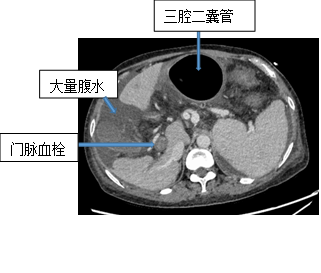

在重症監護病房,消化內科杜井峰副主任醫師在千鈞一髮的時刻及時為湯女士插入了三腔二囊管,出血暫時停止。但險情並未排除,湯女士肝門靜脈高壓,血液隨時「決堤」,時刻威脅生命安全。

但是湯女士情況特殊,她的門靜脈主支以及多個分支有血栓形成,這極大地增加了治療的風險性和難度。徐龍緊急發起了多學科會診。在與患者家屬詳細溝通了手術可能的風險以及做好完善的術前準備後,徐龍帶領團隊為湯女士開展手術治療。在此次治療中,由於湯女士有嚴重的血栓形成,傳統的TIPS治療已經無法實現,在手術室內,徐龍反覆造影、查看患者的腹部血管走行,最終選擇在下腔靜脈與腸系膜上靜脈之間放置了支架,極大地降低了門靜脈壓力,湯女士轉危為安。